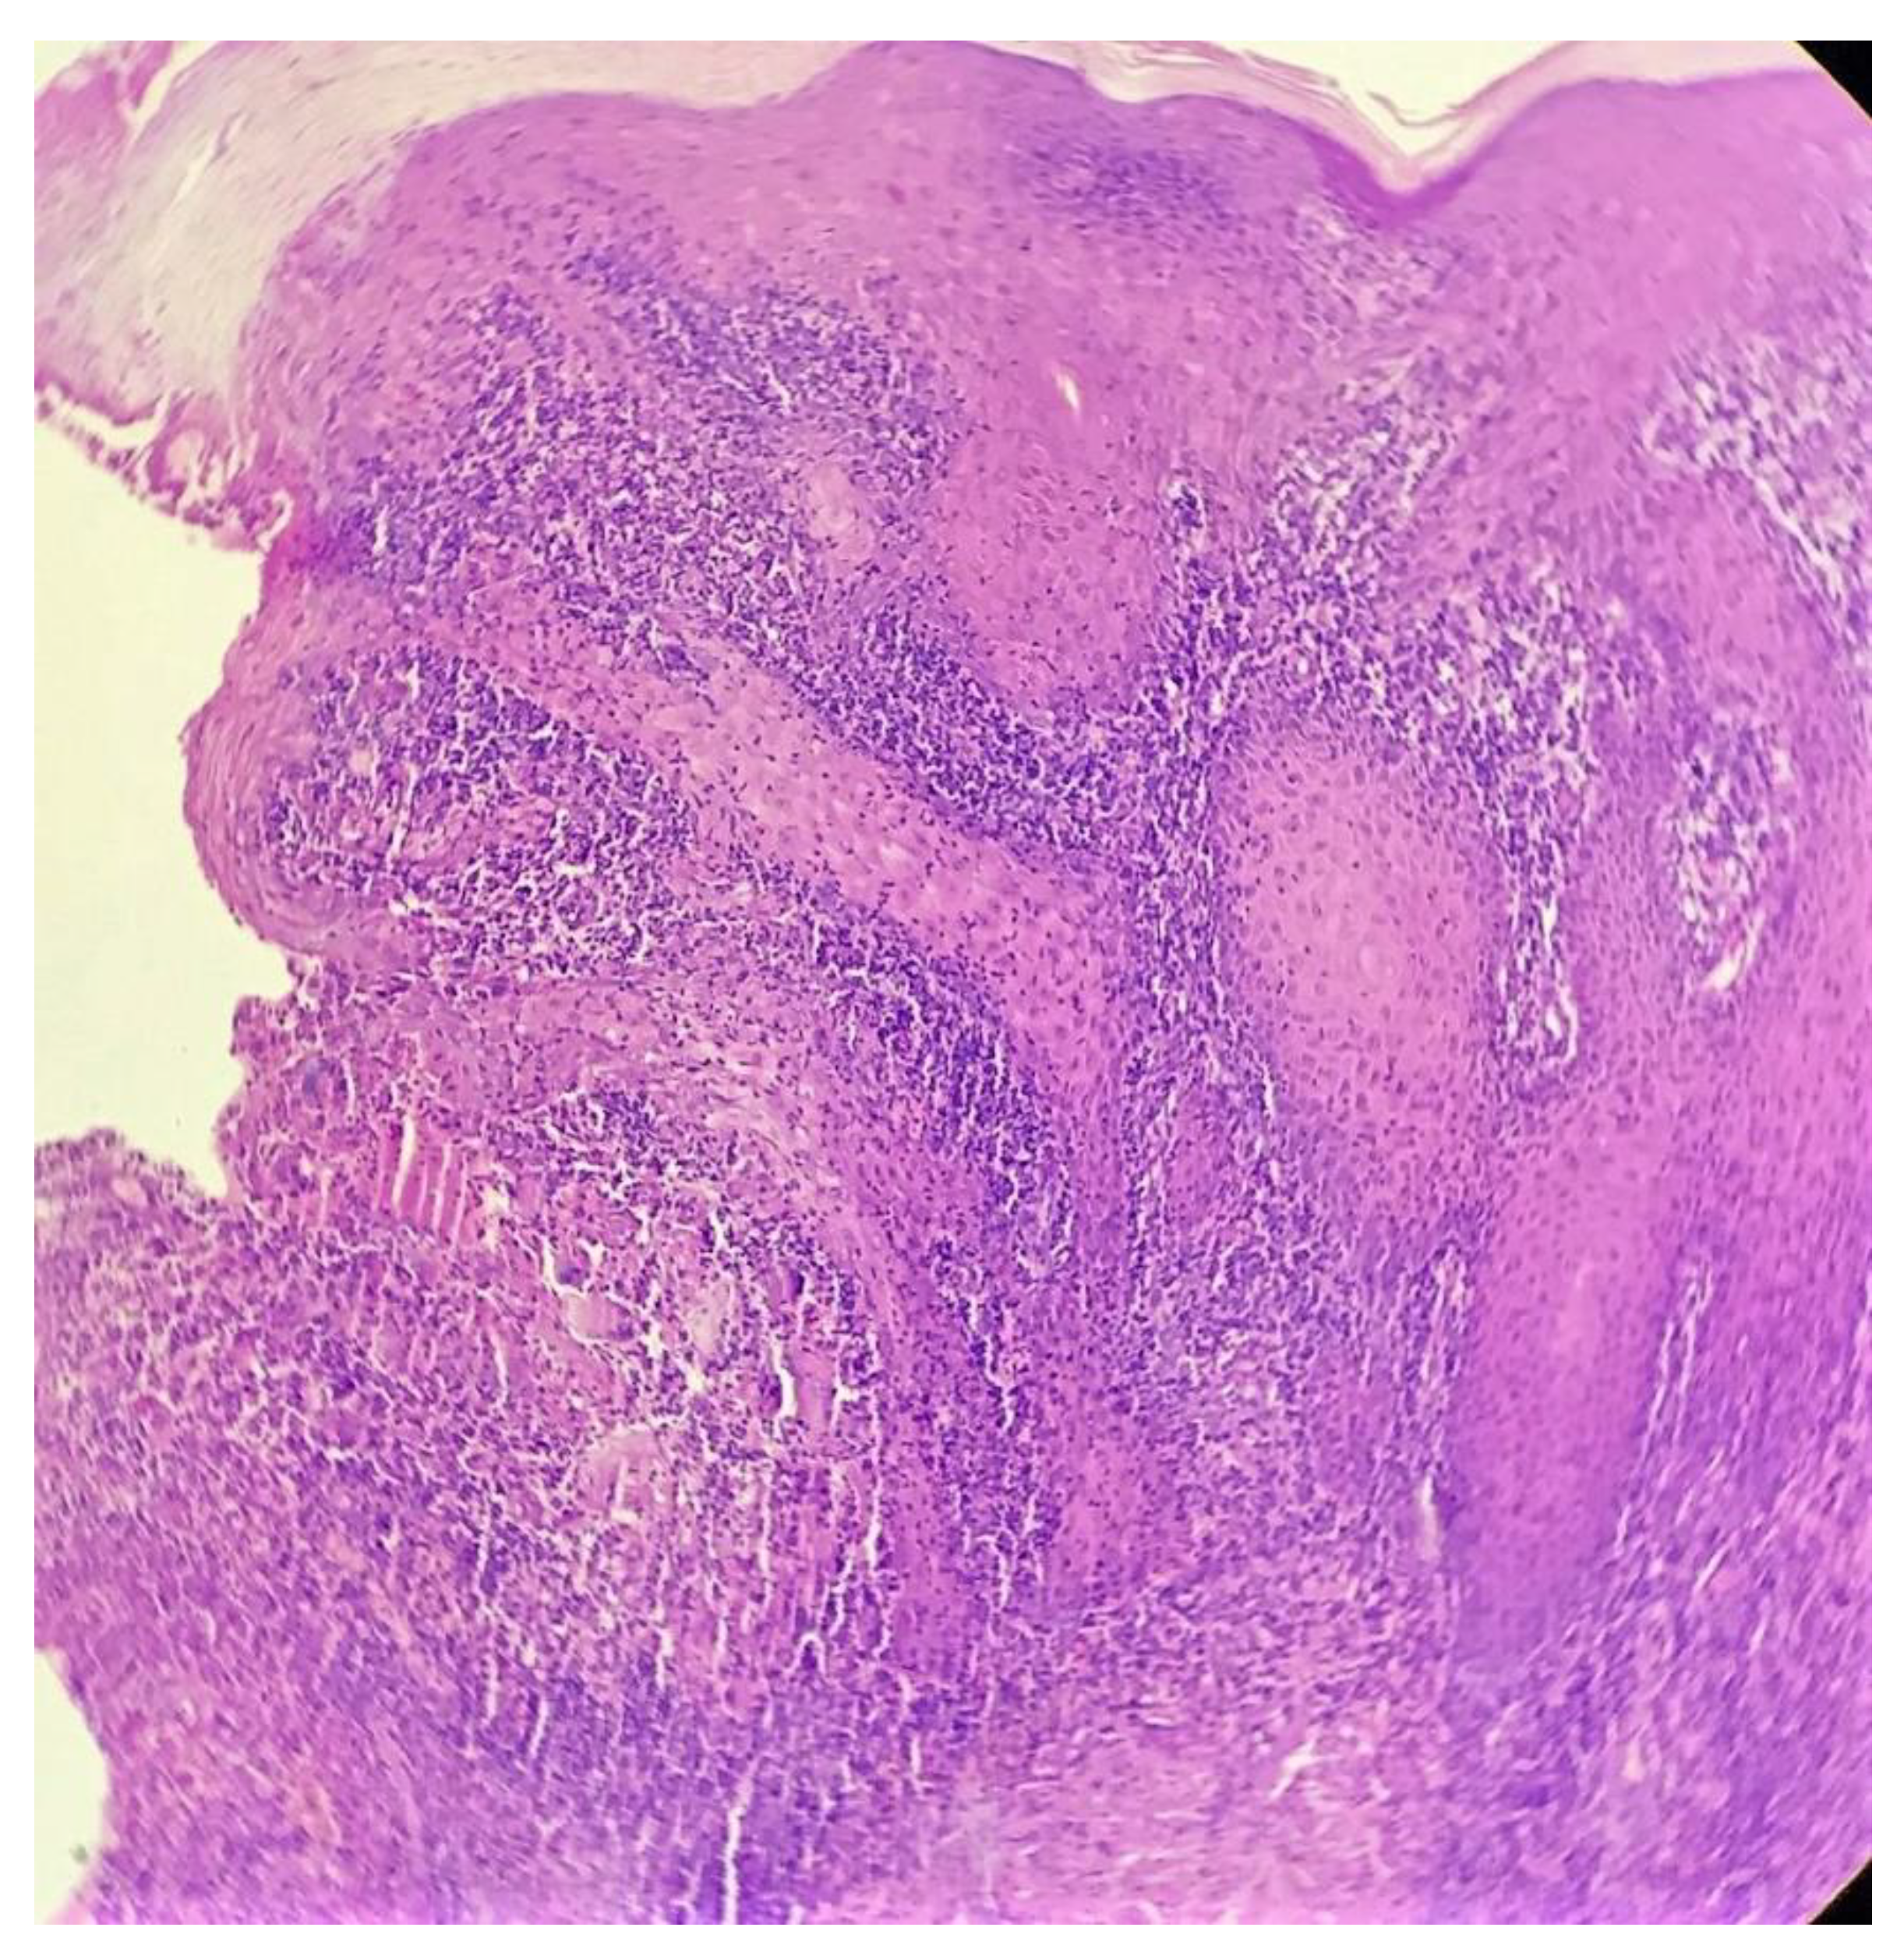

Biopsy showed a dense lichenoid and loose tuberculoid granulomatous infiltrate comprising of epithelioid cells, histiocytes and occasional Langhan’s giant cells, surrounded by lymphocytes and few plasma cells. The granuloma was seen abutting the overlying epidermis, which showed psoriasiform hyperplasia with mild to moderate spongiosis. A compact tuberculoid granuloma was also seen in the deep reticular dermis. Fibroplasia was also seen in the dermis (Figure 2, Figure 3, Figure 4 and Figure 5). The PAS-stained sections were negative for fungal organisms. Zeil–Neelsen stained sections did not reveal any acid-fast bacillus. Based on these features, a diagnosis of lupus vulgaris was favoured and further confirmation by culture study and PCR was advised.

Figure 2. Lichenoid granulomatous dermatitis pattern with psoriasiform epidermal hyperplasia (H&E × 40).

Figure 3. Loose tuberculoid granuloma abutting the overlying hyperplastic epidermis (H&E × 100).